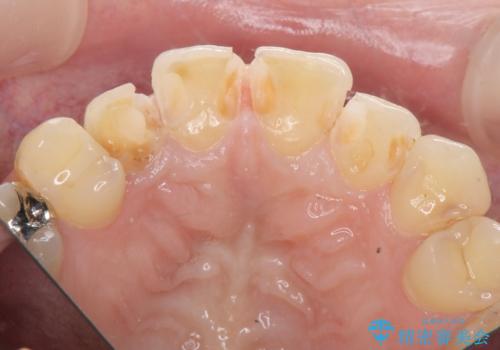

- 神経をとった前歯の変色や、前歯の充填物の変色が大きくなってきたので審美性の改善を求めて来院されました。

充填物や充填物下に再発した虫歯を丁寧に除去し、セラミッククラウンによる審美性の改善、虫歯治療を計画します。

レジン修復による充填は、劣化し、色調の変化による審美障害が生じることが多々あります。

ある程度の大きさになった充填物は、劣化の少ないセラミッククラウンにすることで色調の劣化を抑え、審美性を保つことができます。